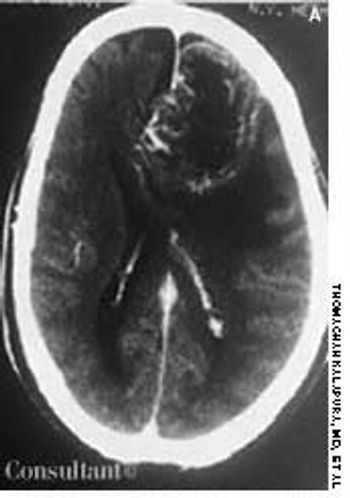

Headache and vomiting suddenly developed in a 41-year-old woman who was 16 weeks pregnant. The next day, she suffered an episode of tonic-clonic seizures associated with a 15-minute loss of consciousness.